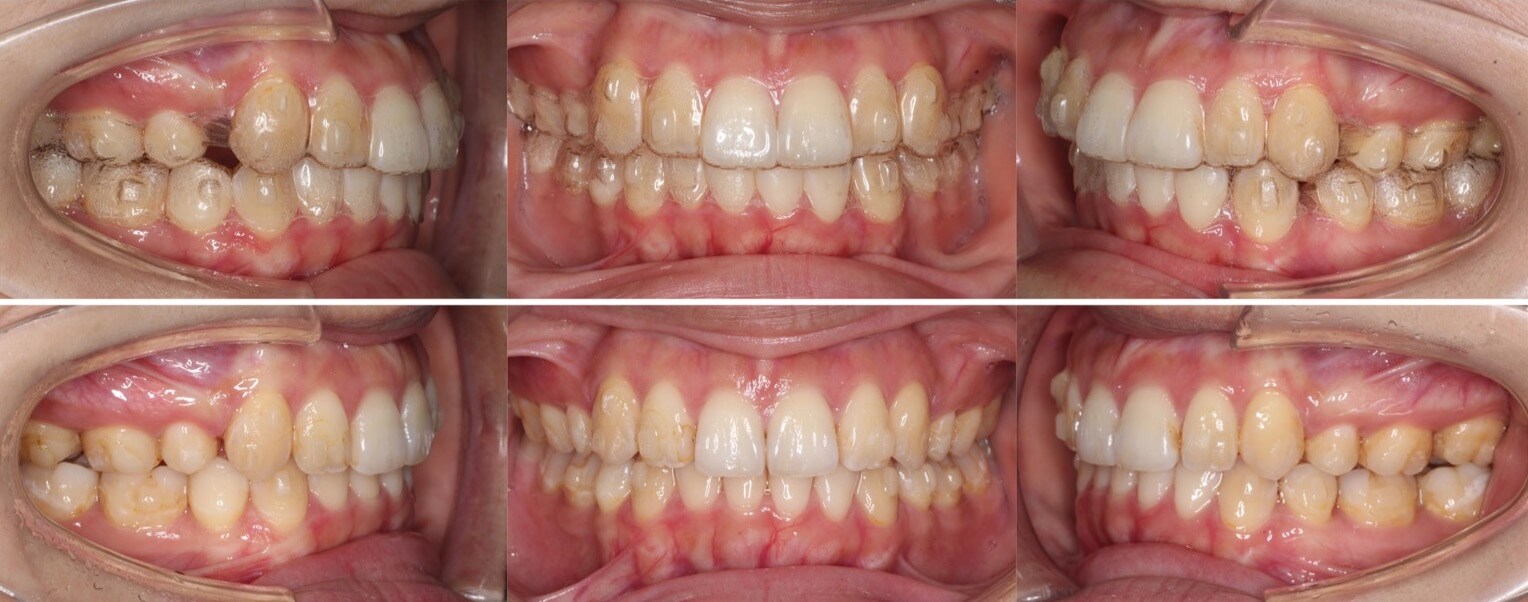

「男性は顔が引き締まる」

高校生男性・唇側矯正装置・下あご後退型

当初は、抜歯矯正治療にするかしないかで、治療方針に迷ったケースですが、最終的には患者さんの希望に沿って抜歯矯正治療にしました。歯の動きがゆっくりであったため、治療期間が3年を超えてしまいました。

<症例概要> 難易度:★★★★☆

主訴:口元の突出・前歯のガタツキ

年齢・性別:高校生男性

住まい:千葉県八千代市市

症状:下顎後退・叢生

治療方針:抜歯空隙の閉鎖(最大固定)

治療装置:唇側矯正装置

固定:歯科矯正用アンカースクリュー(頬側x2)

抜歯:上下第一小臼歯(計4本)

治療期間:3年4か月

リテーナー:上下プレートタイプ+フィックスタイプ

治療費用:968,000(税込)

代表的副作用:痛み・治療後の後戻り・歯根吸収・歯髄壊死・歯肉退縮